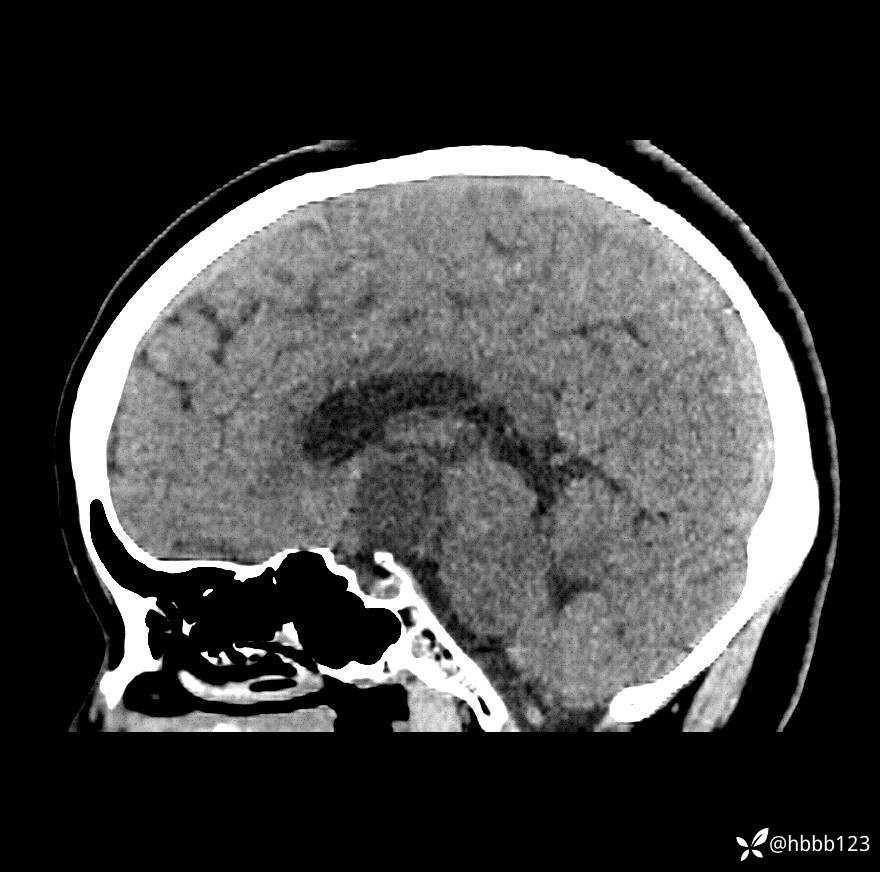

颅脑CT平扫:

矢状位重建: